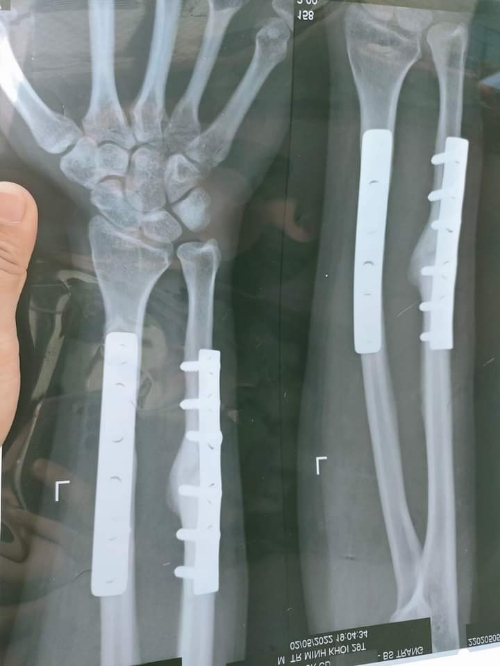

Nẹp vis cẳng tay thẳng trục có hình ảnh can xương , e mổ được bao lâu rồi